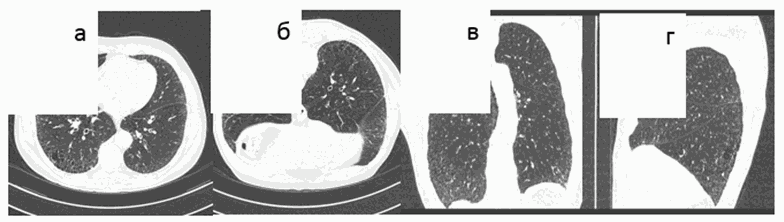

В легких на фоне пневмофиброза и эмфиземы наблюдаются очаги на всем протяжении . Идеопатический гемосидероз легких — заболевание неизвестной природы, при котором периодически происходят внутриальвеолярные кровоизлияния с гемолизом . Частые повторные обострения вызывают развитие диффузного фиброза .

При развитии фиброза легких нарушаются дыхательные функции . Полностью избавиться от недуга не поможет даже своевременное лечение, ведь фиброз можно только приостановить, в том числе и народными средствами .

Эффективное лечение фиброза легких народными средствами . Фиброз легких - это утолщение соединительной ткани, которая является частью перегородок, отделяющих альвеолы легких друг от друга .

Фиброз легких - это утолщение соединительной ткани, которая является частью перегородок, отделяющих альвеолы легких друг от друга . Болезнь приводит к

Фиброз легких обычно не лечится, потому что это уже конечная стадия воспалительных процессов и она необратима . Если площадь фиброзных образований невелика, то на работоспособность легкого это почти не влияет . Наблюдают и предупреждают и лечат осложнения . Фиброзная ткань затрудняет передачу кислорода в кровь, что приводит к